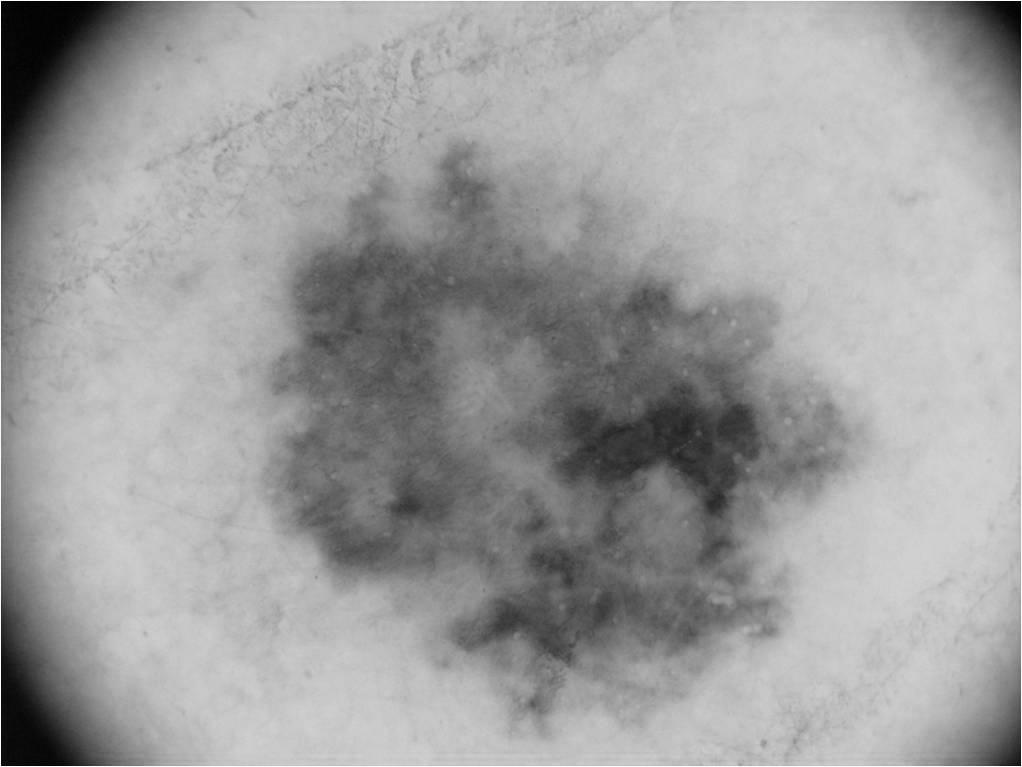

A Biblioteca Digital reúne imagens dermatoscópicas em três fases (Original, Gray e Segmentação), associadas ao mesmo caso clínico por ID para apoio à decisão médica baseada em evidência visual.

Exemplo real de saída segmentada com fundo preto e lesão destacada, componente técnica central da dissertação.